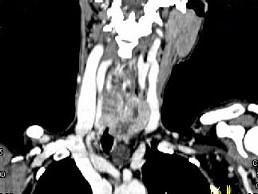

问题 女,50岁,左下颈部扪及一质硬、表面高低不平的包块,肿块逐渐增大,现感吞咽困难,CT如图所示,最可能诊断为 ( )

选项 A、甲状腺原发淋巴瘤 B、颈部神经鞘瘤 C、食管癌 D、喉癌 E、甲状腺癌

答案 E